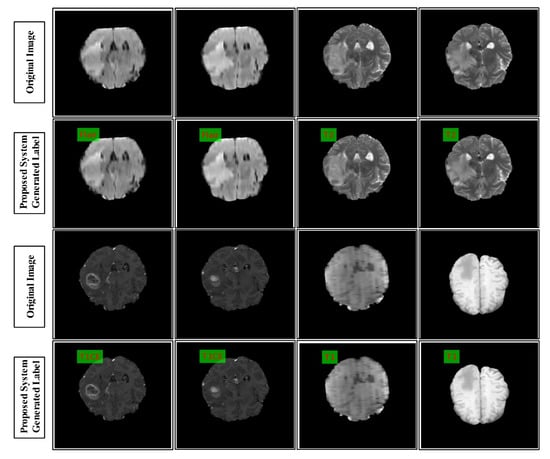

3.7. Results for the BraTS 2015 Dataset

3.8. Results for the BraTS 2017 Dataset

3.9. Results of the BraTS 2018 Dataset